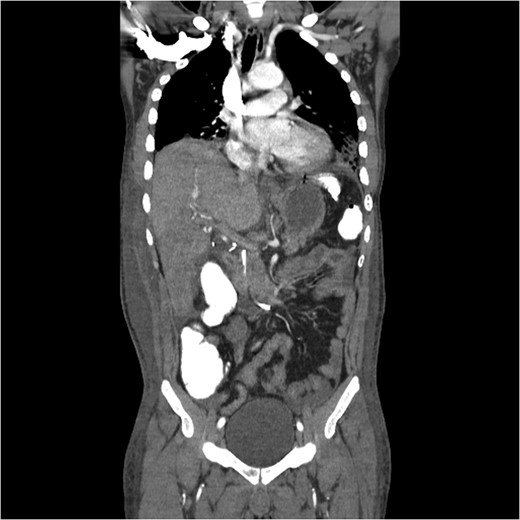

A computed tomography (CT) angiogram of the abdomen was significant for multifocal pneumonia and free peritoneal fluid. Chest CT was negative for pulmonary embolism (Figs 1, 2). Repeat ERCP confirmed a wide-open distal common bile duct at the level of multiple surgical clips with inability to pass a wire distally (Fig. 3). Interventional radiology was consulted to obtain a percutaneous transhepatic cholangiography (PTC) prior to definitive surgical repair.

Coronal CT image with partially visible ERCP stent in the distal common bile duct with surrounding clip artifact.